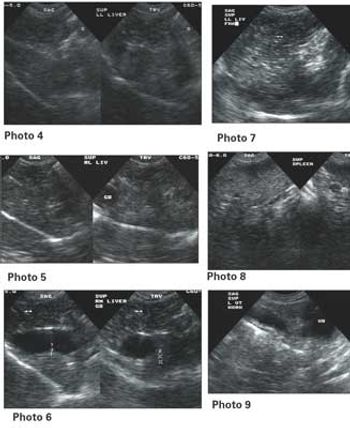

Signalment: Canine, Greyhound, 2.5 years old, female spayed, 65 lbs. Clinical history: The dog has a persistent urinary tract problem ? hematuria for at least one year according to the owner. The dog improves with antibiotics, but once finished, hematuria starts again. Therapy has included Clavamox.